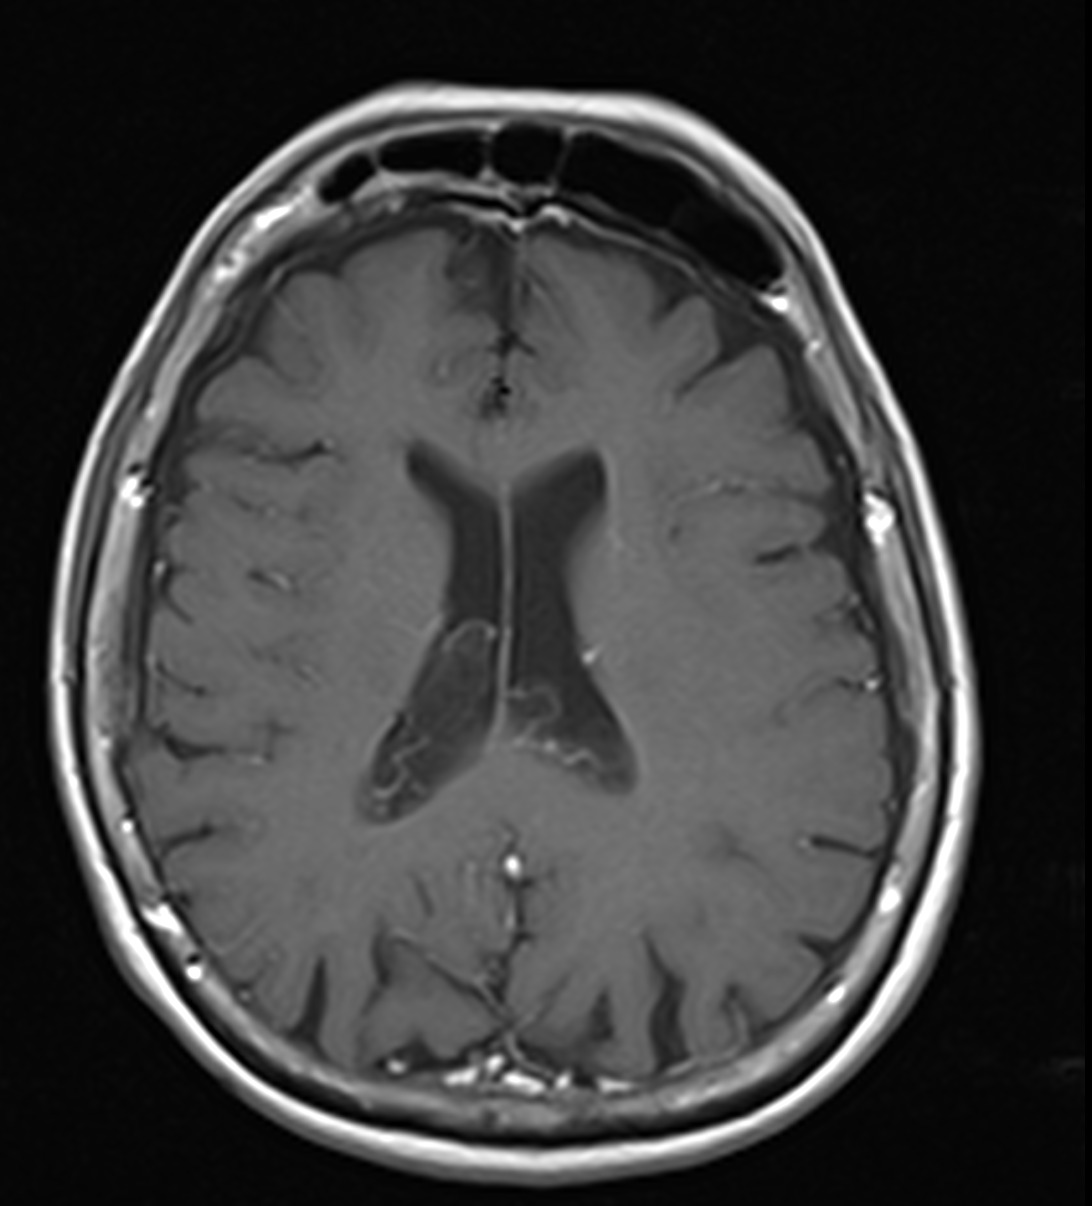

Son pseudolesiones frecuentemente observadas en estudios de neuroimagen.

Sus principales características son:

✔ Lesiones intraventriculares

✔Bilaterales

✔65% restringen en la secuencia de difusión

✔ Realce variable posterior a la administración de medio de contraste

✔ No hay edema del parenquima adyacente

NO DEBEN CONFUNDIRSE CON LESIONES TUMORALES INTRAVENTRICULARES!!!!